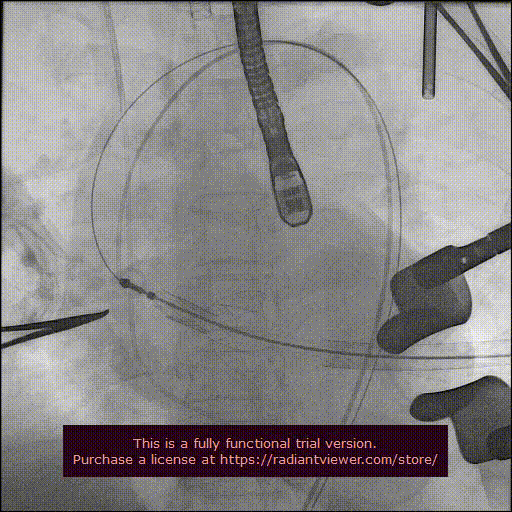

造影显示主动脉窦部

从心尖置入输送系统

定位件入窦

瓣膜降至瓣环平面

释放瓣膜

造影确认瓣膜位置

撤出输送系统

造影确认植入效果